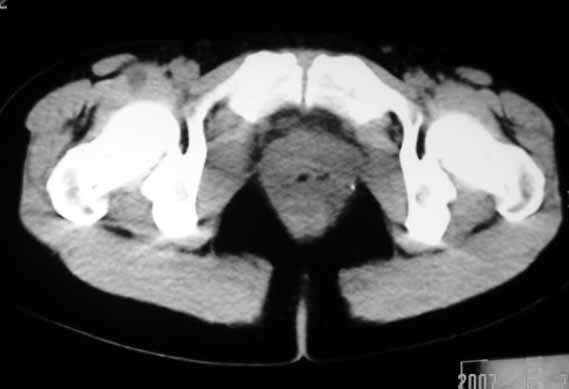

标题: CT8123:女46岁,左下腹胀痛不适1月,以前曾有月经过多史,现已 [打印本页]

标题: CT8123:女46岁,左下腹胀痛不适1月,以前曾有月经过多史,现已

子宫肌瘤,不强化不好说

考虑子宫们内膜癌并右侧腹股沟淋巴结转移

子宫增大密度较均匀,考虑子宫肌瘤,不强化不好说

考虑子宫肌瘤(变性)或子宫腺肌病,不排除内膜ca可能,不增强建议结合mri或b超检查。

子宫们内膜癌或子宫颈癌体部浸润并右侧腹股沟淋巴结转移

子宫增大密度较均匀,考虑子宫肌瘤可能性大,